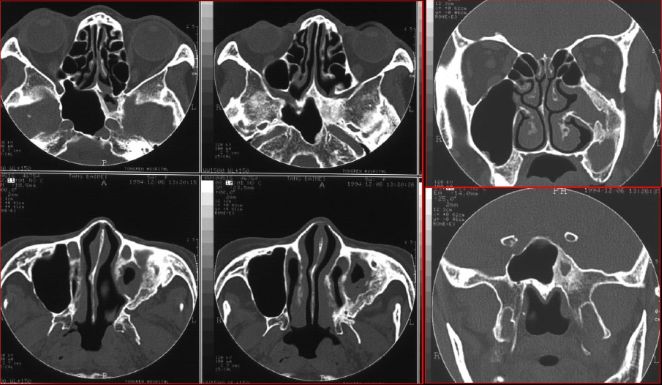

蝶窦炎—眶尖综合症

鼻窦炎—眶尖综合症